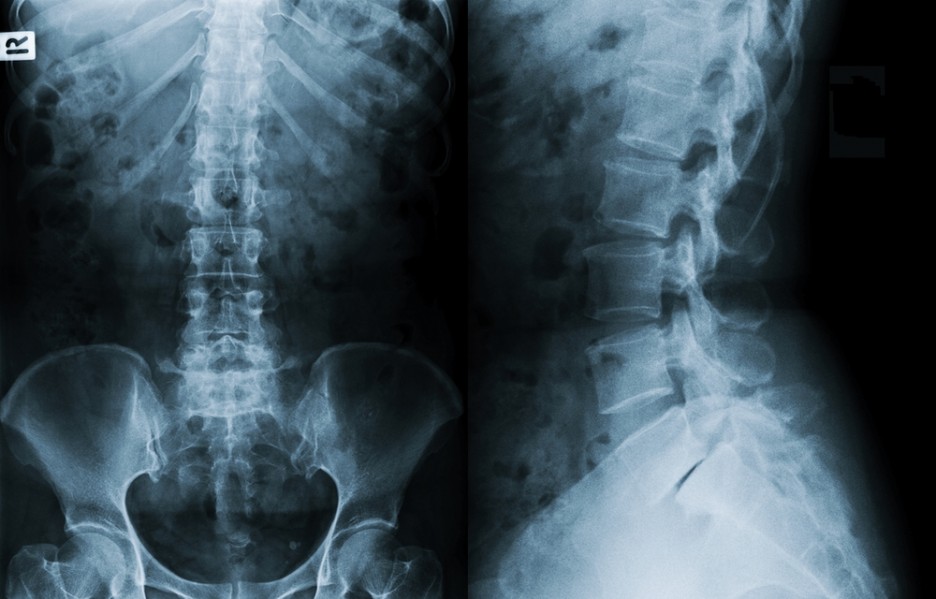

1. 단순 방사선 검사(X-ray)

1) 뼈의 구조를 전반적 구조를 볼 수 있습니다.

2) 디스크의 파열 정도나 인대 같은 연부 조직은 보이지 않기 때문에

디스크의 상태를 알기 위해서는 CT나 MRI가 필요하답니다.

* X-ray로 확인할 수 있는 것 :

뼈의 구조, 척추의 정렬, 골절, 인대의 골화, 석회 침착